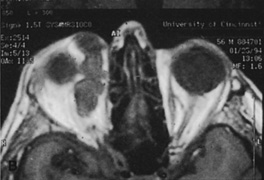

The other important consideration in planning orbitotomy is the position of the tumor within the orbit. Lesions generally may be categorized as either anterior (superficial) or posterior (deep). They can be further categorized by their relationship to the optic nerve (medial, lateral, superior, or inferior to the optic nerve). It may be helpful to further classify the location of lesions relative to adjacent anatomic structures in the orbit. Many surgeons prefer to conceptualize orbital pathologic processes as being located within one or more of seven “surgical spaces” within or around the orbit (Fig. 5). These spaces include:

Fig. 5. Axial drawing of anatomic spaces of the orbit. (1, intraconal space; 2, extraocular muscles; 3, peripheral surgical space; 4, subperiosteal space; 5, preaponeurotic space; 6, Tenon's space; 7, periorbital tissues.)